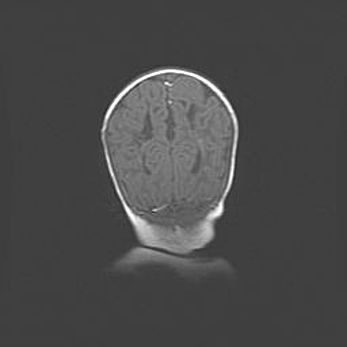

Открытая гидроцефалия.

Возраст: 6 месяцев 15 дней

Вес: 6200 г

Пол: женский

Окружность головы: 41 см

Срок гестации: 38 недель

Гидроцефалия головного мозга у новорожденных – это скопление избыточного количества цереброспинальной жидкости в головном мозге. Ее избыточное скопление в мозге приводит к патологическому расширению желудочков мозга (четырех полостей, расположенных в глубине белого вещества мозга, заполненных цереброспинальной жидкостью и связанных узкими проходами).

Открытый тип гидроцефалии (сообщающаяся) наблюдается тогда, когда нарушен механизм всасывания ликвора в системный кровоток. При этом типе причиной заболевания чаще всего является перенесенные ранее инфекции (например: менингит),  либо же наличие крови в субарахноидальном пространстве.